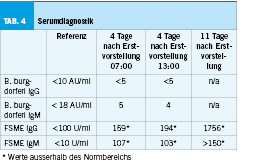

In der im Verlauf erfolgreich durchgeführten Liquoranalyse (Tabelle 2) war eine Pleozytose mit erhöhtem Proteinanteil sichtbar, bei einer leicht- bis mittelschweren Störung der Bluthirnschranke. Zweizeitig bestimmte FSME-Serologien (sowohl IgM- als auch IgG-Antikörper) fielen jeweils positiv aus (mit deutlichem Titeranstieg (Ausgangswert IgG-Antikörper: 159 U/ml; im Verlauf 1756 U/ml)), während der HSV-Typ 1/2- sowie VZV-PCR negativ ausfiel (Tabelle 3). Die empirische Therapie mit Rocephin, Aciclovir sowie Dexamethason wurde folglich gestoppt.